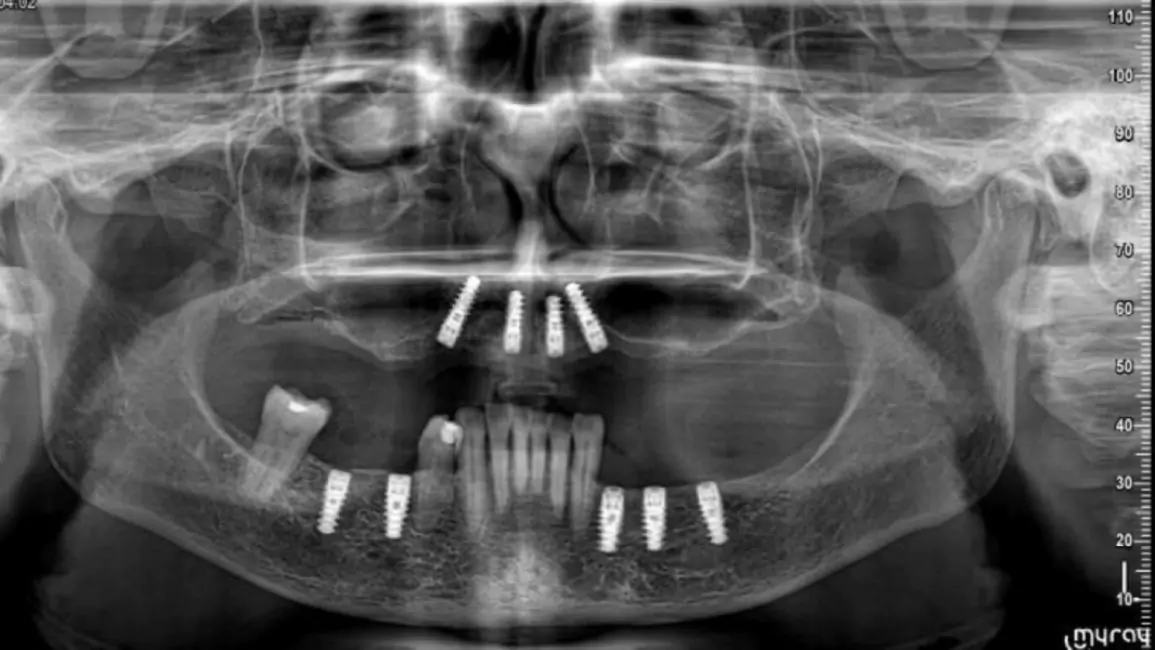

Since year 2000 we are Centre of excellence in implantology .We have done thousands of full mouth dental implant cases in last 25 years .We have a team approach where experienced implant surgeons , prosthodontists , maxillofacial surgeons , digital restorative dentists and lab technicians work together to deliver world class fixed teeth. We use multiple implant option from case to case. Some need All-on-4, some need All-on-6 or All-on-8 in selective cases.

The procedure of Full Mouth Dental Implants involves, extraction of teeth or root of the existing teeth if any, CBCT Scans and X-ray, Planning of implant placement, procedure of Implant placement, healing, temporary prosthesis and then a final prosthesis restoration, giving a perfect smile, functionality and appearance.

How are dental implants replaced in the mouth?

Implants are placed based various factors, prominent being 0the bones density for implant placement, every procedure is done using the advanced technology, such as CBCT guided implant placement, while also Implant torque is considered crucial. These all things are considered to place implants strategically to support Full Mouth Teeth Replacement, for functionality, durability and aesthetics.